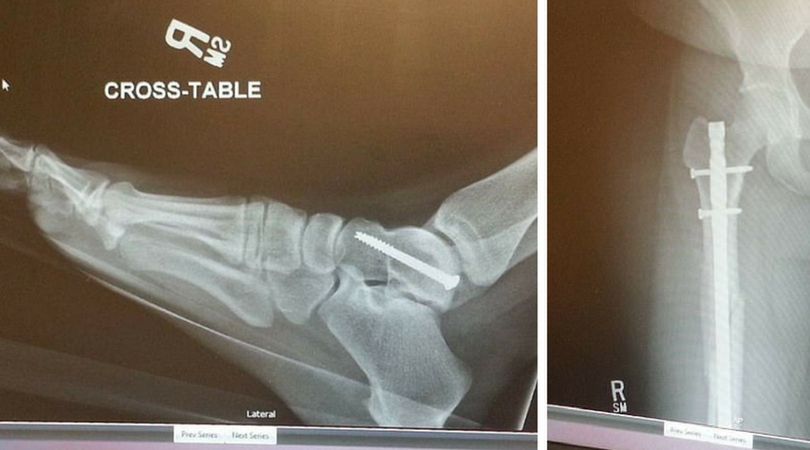

Dzisiaj kobieta musi żyć z dwiema śrubami w kostce, w udzie, a także w kolanie. Nie może stać w ciągu dnia dłużej niż 4 godziny.

Lekarze musieli zamontować w kostce Audry specjalne śruby

Lekarze musieli zamontować w kostce Audry specjalne śruby © (facebook.com) Lekarze musieli zamontować w kostce Audry specjalne śruby

Audra spędziła na leczeniu w szpitalu tylko 3 dni, a nie 10, jak być powinna. Rodziny nie stać było ma rehabilitację, więc jej leczenie w początkowych fazach było prowizoryczne. Niestety, po ponad roku od wypadku, Audra jest trwale niepełnosprawna. Nie może przebywać w pozycji stojącej dłużej niż parę godzin dziennie. ''Nie mogę ustać na nogach dłużej niż 3-4 godziny. Po tym czasie mam nogi jak z waty i czuję straszny ból'' – powiedziała.